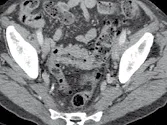

Figure 1. Patient porteur de métastases hépatiques de cancer colique.

Sur l’examen initial (A, B), il existe de multiples lésions secondaires.

Deux cibles sont choisies dans le foie droit, une à hauteur de la bifurcation portale (A) une autre dans le segment VI (B). D’autres lésions mesurables existent, mais seront considérées comme non cible (A). Après six mois de chimiothérapie (C, D), on observe une progression des cibles, des non cibles, et une nouvelle lésion indiscutable dans le segment VI (D)